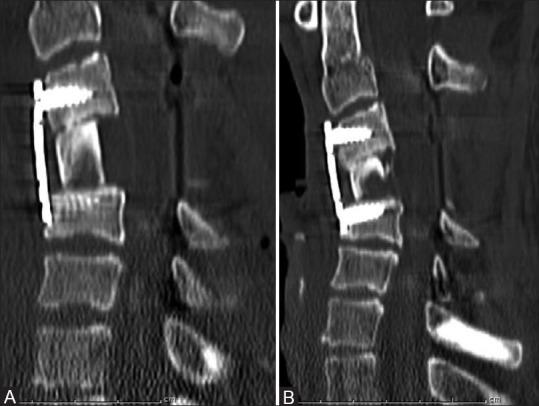

多节段颈椎椎体次全切除术后使用长支撑植骨特有的并发症:先进成像技术的应用

Complications exclusive to long strut grafts used following multilevel cervical corpectomy: Utilization of advanced imaging techniques.

When surgical decompression of cervical spine is considered, multilevel cervical corpectomy with long strut grafts is the preferred treatment. This procedure is used in a variety of pathologies including degenerative disease, tumors, trauma and infection. Corpectomy with interbody grafting helps in adequate spinal canal and neural decompression compared to multilevel discectomy, which could be difficult as well as inadequate. Fibular/iliac strut grafts are used for reconstruction along with a stabilizing hardware in this procedure. So far, complete imaging spectrum of complications exclusive to strut graft has not been reported in the literature. This pictorial essay presents complications exclusive to the strut graft, utility of advanced imaging in diagnosis and a brief note on the clinical management of complications.

摘要

当考虑进行颈椎手术减压时,多节段颈椎椎体次全切除并使用长支撑植骨是首选的治疗方法。该手术适用于多种病理情况,包括退行性疾病、肿瘤、创伤和感染。与多节段椎间盘切除术相比,椎体次全切除并椎间植骨有助于充分减压椎管和神经,因为多节段椎间盘切除术可能既困难又不充分。在此手术中,使用腓骨/髂骨支撑植骨并结合稳定的内固定器械进行重建。到目前为止,文献中尚未报道过支撑植骨特有的完整并发症影像学谱。这篇影像文章介绍了支撑植骨特有的并发症、先进影像学在诊断中的作用以及并发症临床处理的简要说明。